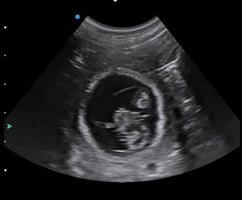

Imagine this clinical scenario: a client brings in their pet dog that is presenting with acute abdominal signs. After talking to the owner, you suspect an intestinal obstruction which, if diagnosed, could require surgical intervention. You recommend carrying out some diagnostic imaging tests to identify any intestinal obstructions, including an abdominal radiograph and ultrasonography.

Due to the client’s financial constraints, you can only use one diagnostic imaging method. You decide to consult the evidence to find out whether radiography or ultrasonography is superior at detecting the need for surgical intervention by accurately diagnosing small intestinal mechanical obstruction.

Winter et al. (2017) was the only paper that studied the use of ultrasonography without radiography. The paper studied 16 dogs that were suspected of having a complete or partial gastrointestinal obstruction. The outcomes studied were sensitivity, specificity, positive predictive value (PPV) and negative predictive value (NPV) of ultrasonography in the diagnosis of gastrointestinal obstruction.